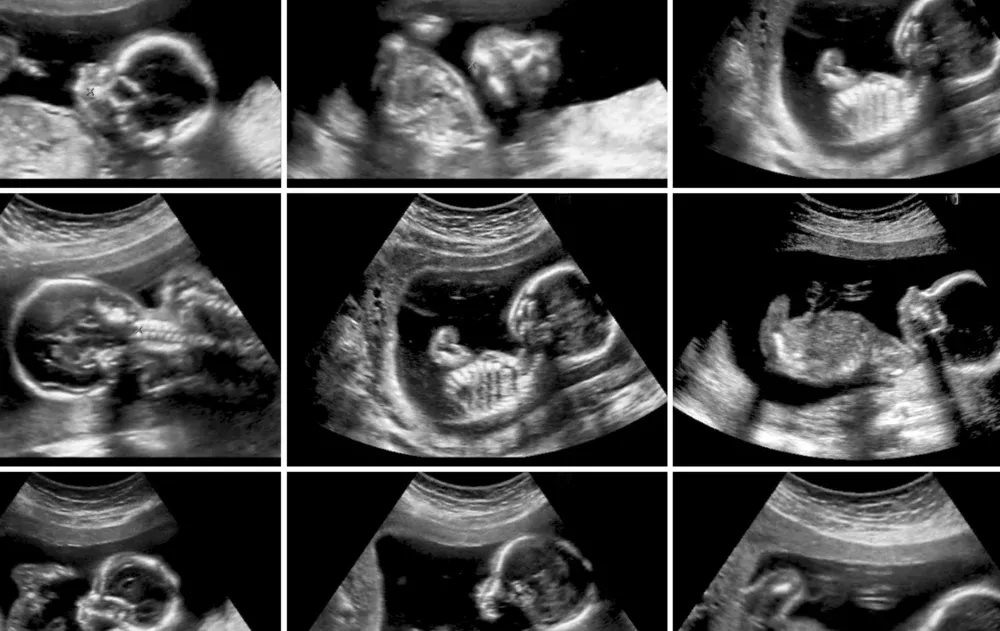

הרופא הביט במסך האולטרסאונד, כיוון עוד פעם את המתמר - ונשאר המום. אחרי רגע קצר של שתיקה, הוא בישר לה בעדינות: "את נושאת ברחמך תשעה עוברים." כן, תשעה. לא טעות, לא כפל - אלא תשיעייה של ממש.

המקרה, מן הנדירים שנראו ברפואה המודרנית, עורר מיד עניין ציבורי אדיר במצרים. כלי תקשורת במדינה דיווחו בהרחבה, ורופאים בכירים התראיינו והסבירו את הסיכון הבריאותי והמורכבות שכרוכים בהריון שכזה.

לפי הדיווחים, האישה נטלה תרופות פוריות - ככל הנראה ללא פיקוח רפואי צמוד - דבר שיכול להסביר את ריבוי העוברים. רופא בשם ד"ר ואהיל אל-בנא צוטט אומר שבעידן הרפואי של היום יש דרכים לנהל הריון כזה - אך אין ספק שמדובר באתגר גדול הן לאם והן לצוות הרפואי.